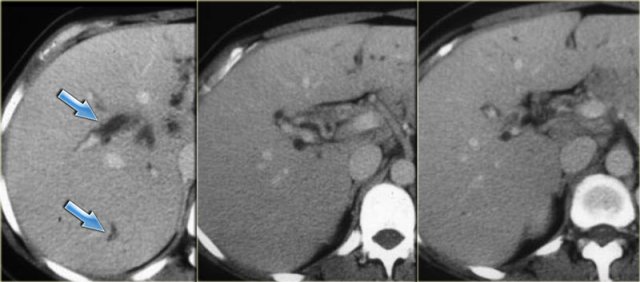

Late CT features are seen on the images on the left.

Study the images and then continue reading.

The findings are:

- Morphologic changes of cirrhosis (volume loss in the right lobe and a large caudate lobe (arrow)

- More pronounced dilatation of the bile ducts

Cholangiography is used in the initial diagnosis of the disease, when there are only subtle strictures and in patients known with PSC to look for new strictures that are suspicious for carcinoma.

On cholangiography we can see:

- Beading: alternating pattern of strictures and normal or slightly dilated ducts

- Pruned-tree: distal bile ducts are narrowed and difficult to see

- Mural irregularity: irregular luminal margin (best seen on the left in the extrahepatic duct)

- Diverticula: best seen in the next patient

On the left the typical findings in PSC.

Notice the diverticula on the image on the right.

Diverticula are very specific for the diagnosis PSC.

So when you see these diverticula, you should immediately search for subtle strictures in the intrahepatic ducts.